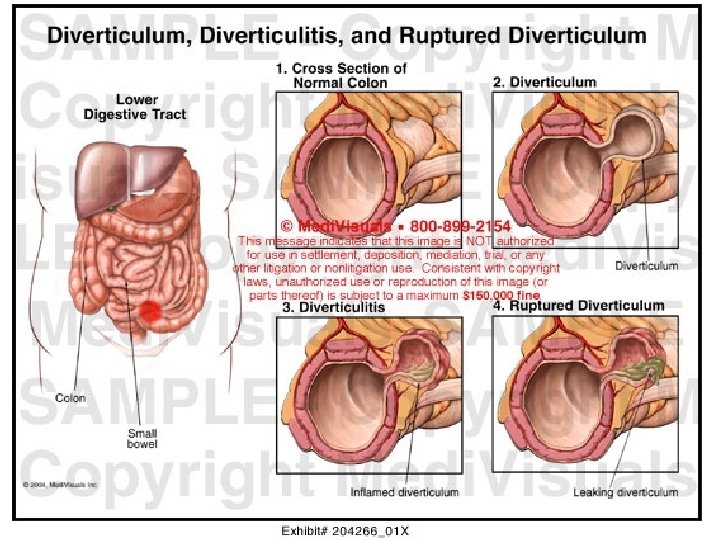

• DIVERTIKULITIS- PERFORIM- GJAKDERDHJE:

Diverticulosis • Diverticulosis is a condition in which the mucosa and muscularis mucosae herniate through the muscularis propria of the colon wall and produce a saccular outpouching. The major risk factor for developing diverticular disease is a low-fiber diet. The incidence increases with age, being rare before the age of 40 and affecting 50% of people over age 75. Only 10 -15% of patients will develop symptoms of the disease like pain, diarrhea, melena, or distention. Approximately 70% of diverticula occur in the sigmoid colon and 25% in the ascending colon. Most appear on the antimesenteric side of the colon, between taenia. Plain films and barium studies reveal diverticula as gas/barium-filled sacs parallel to the lumen of the colon. Most are 5 -10 mm in diameter, but may range from tiny spikes to 2 cm. The muscular layer may appear thickened with a distorted luminal contour in CT. Patients are managed with fiber supplements and stool softeners.

• Divertikulitis-simptomat: